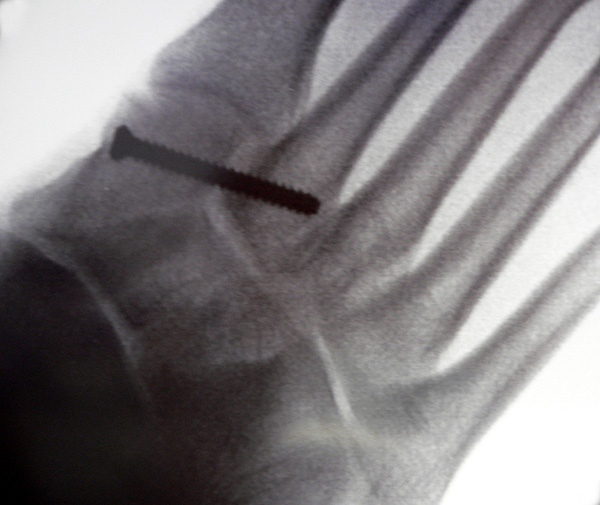

Bei frischen Verletzungen gelingt meist die geschlossene Reposition durch eine Repositionszange unter Bildverstärkerkontrolle. Anschließend wird über eine kleine mediale Inzision ein Kirschnerdraht vom Os cuneiforme mediale in die Metatarsale II-Basis gebohrt und das Lisfranc-Ligament durch eine Stellschraube in anatomischer Stellung ruhiggestellt. Durch weitere Schrauben lässt sich bei Bedarf das Tarsometatarsale I-Gelenk und der Raum zwischen Os cuneiforme I und II stabilisieren. Nach Lagekontrolle unter dem Bildverstärker wird eine durchbohrte Schraube mit durchgehendem Gewinde eingebracht (Abb. 14). Von der Verwendung von Zugschrauben wird abgeraten, da diese eine unnötige und unphysiologische Kompression der Gelenkflächen erzeugen.

Zum Lesen der Bildbeschreibung und zur Vollansicht bitte das Bild anklicken.